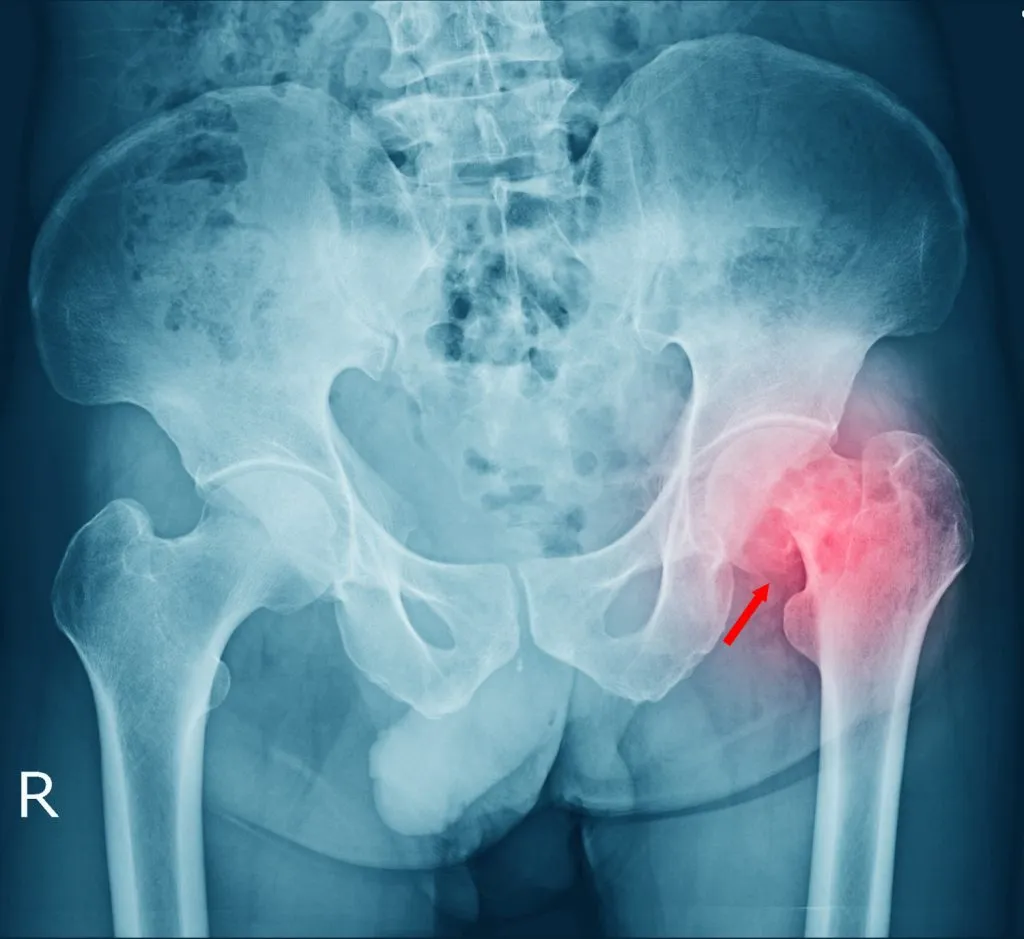

- X-rays: To visualize the break and determine the type and severity of the fracture.